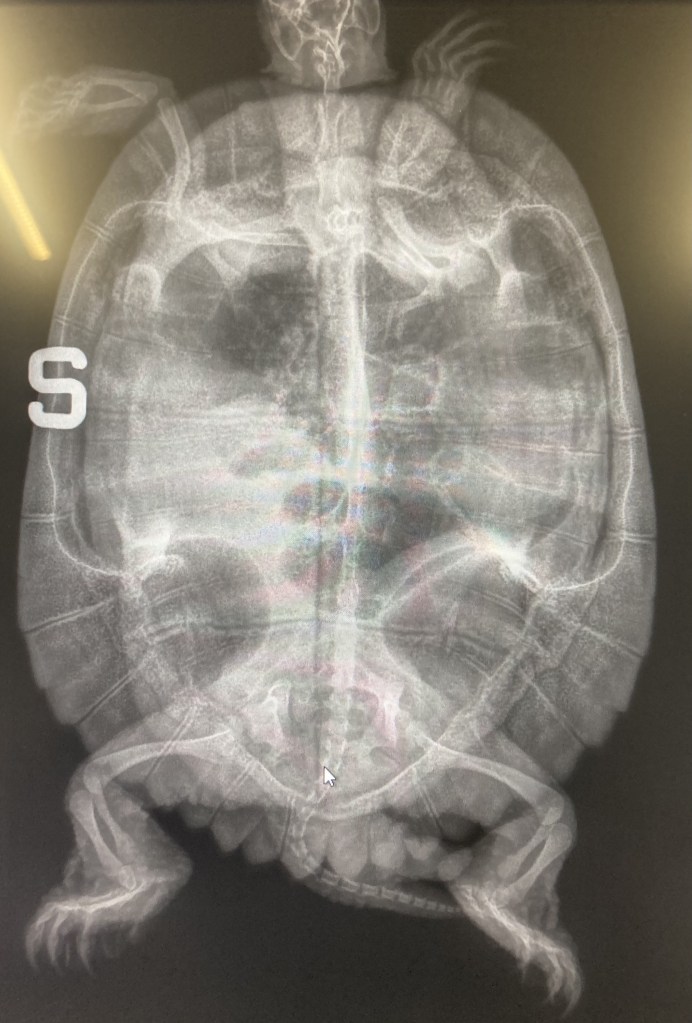

CONSULENZA VETERINARIA PER LA SALUTE E IL BENESSERE DELLE TARTARUGHE

DOTT. MARCELLO BALZARETTI

Il Dott. Marcello Balzaretti, laureato a pieni voti in Medicina Veterinaria presso l’Università’ Statale di Milano e iscritto all’Ordine dei Medici Veterinari di Milano (n. 3999) e’ un libero professionista che si occupa di medicina dei cheloni garantendo la salute e il benessere delle tartarughe di terra e delle tartarughe palustri sul territorio nazionale.